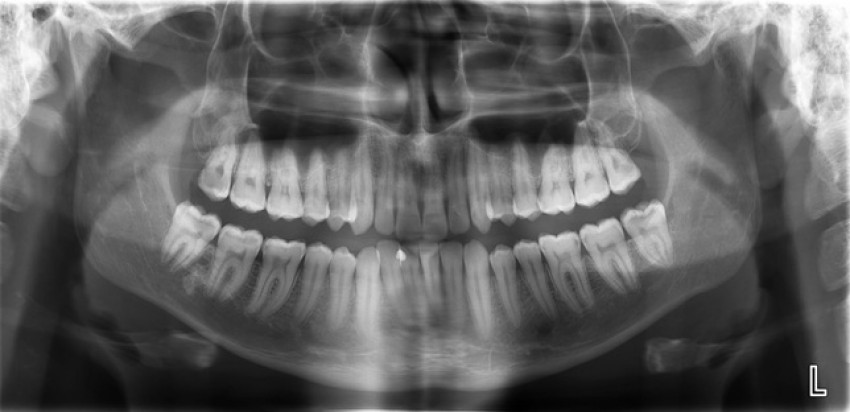

Răng khôn mọc lệchHình ảnh thứ 2 (hiếm gặp).

Phim X quang tiếp theo này (hình 2) cho thấy một ví dụ tuyệt vời về vị trí mọc chính xác của răng khôn. Những chiếc răng khôn này mọc khá thẳng hàng (tương đối giống trường hợp của tôi). Nhưng thật không may, mặc dù mọc thẳng và đúng vị trí nhưng bệnh nhân này vẫn không thể vệ sinh được răng khôn nằm trong cùng tận góc hàm và trên phim đã phát hiện có một số lỗ sâu răng khá lớn trong những chiếc răng khôn này. Tại thời điểm chụp phim này, nha sĩ và bệnh nhân sẽ phải thảo luận về việc hàn chúng hay loại bỏ chúng. Và trong trường hợp này, bệnh nhân được thống nhất là hàn bảo tồn và tiếp tục theo dõi chúng.